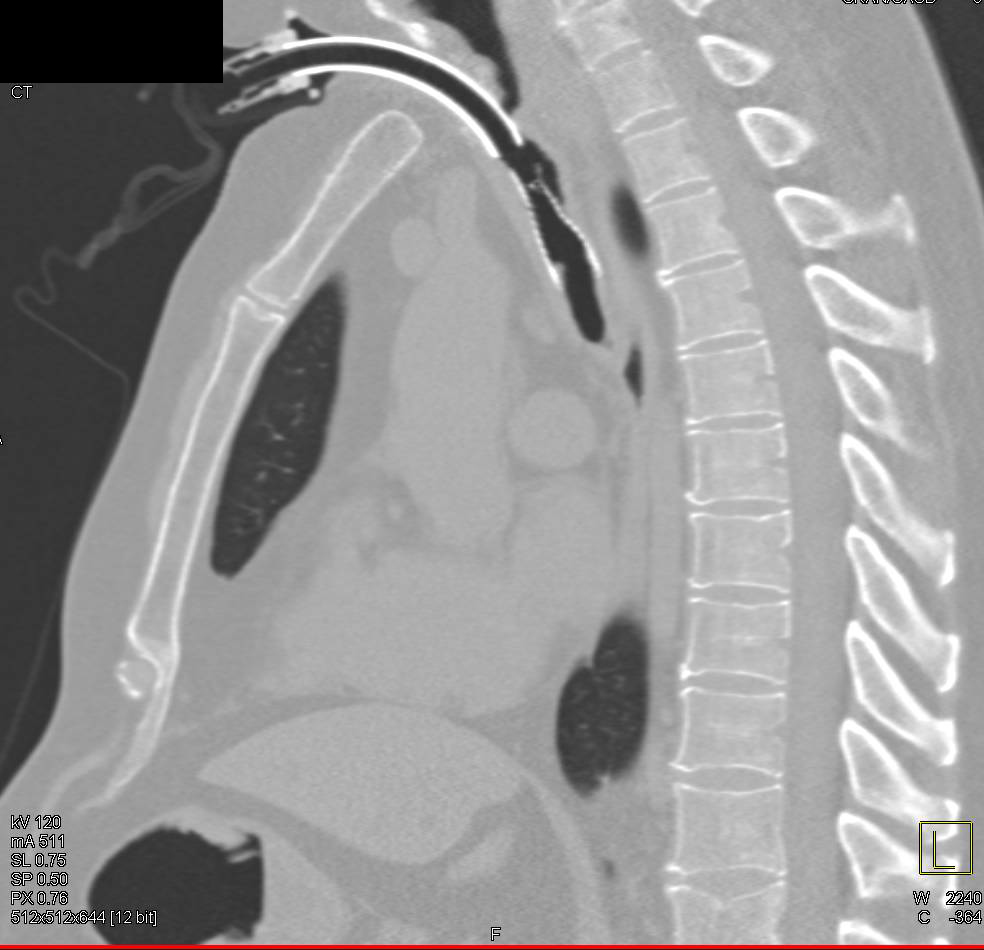

Pulmonary Embolism in patient s/p MVA